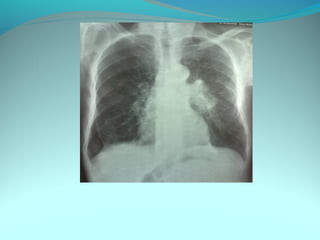

Opacité latéro_trachiale et hilaire droite grossierement arrondie de

6cm de diam dense et homogene

 la limite interne se confend avec le mediastin et la limite externe

nette convexe vers le mediastin

elle confond avec le mediastin évoquant une image mediastinale

Par ailleur on note:

Une surrélevation de la coupole diaph

Un coblement …..

DIAGNOSTIC:

Lymphome H ou NH

Volumineuse ADP tuberculeuse ou sarcoidosique